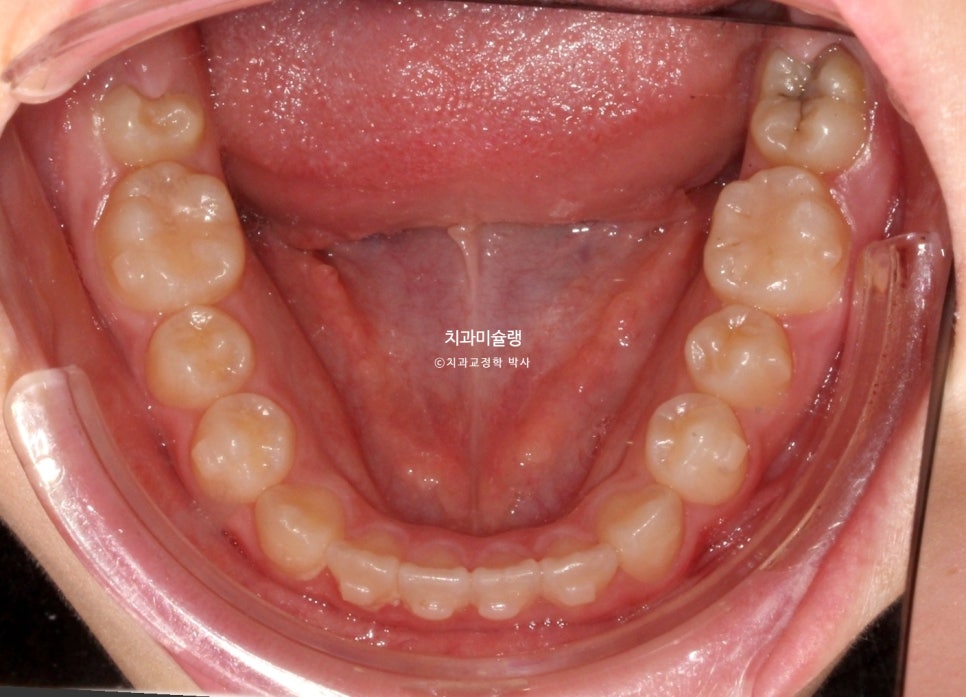

7개월간 36개 장치를 낀 후 모습 입니다.

덧니는 잘 내려왔고 앞니 배열은 좋으나 개방교합과 절단교합이 남아있습니다.

어금니 교합관계 개선을 위한 3급 고무줄을 열심히 끼도록 당부했죠.

배열은 가지런히 정돈되었네요. 그사이 남아있던 유치가 빠지고 영구치가 올라오고 있습니다.

미진한 부분의 개선을 위해 바로 재제작에 들어갑니다.

추가장치 갯수는 11개입니다.

초기 장치는 1주에 하나씩 교체했고 후반부는 장치당 2주씩 끼며 고무줄 끼는 시간을 늘렸습니다.